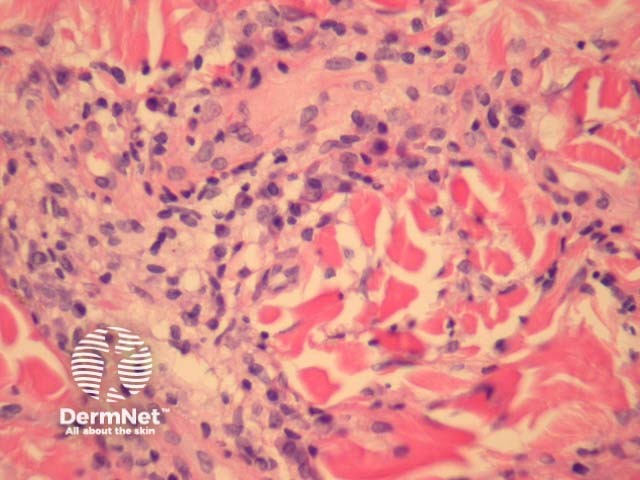

Lesions of acrodermatitis chronica atrophicans can show a similar histopathology but the infiltrate is denser (figure 3). The infiltrate consists of lymphocytes and often there are numerous plasma cells (figure 4) admixed with mast cells. There may be impressive superficial sclerosis and fibroplasia.

Figure 4